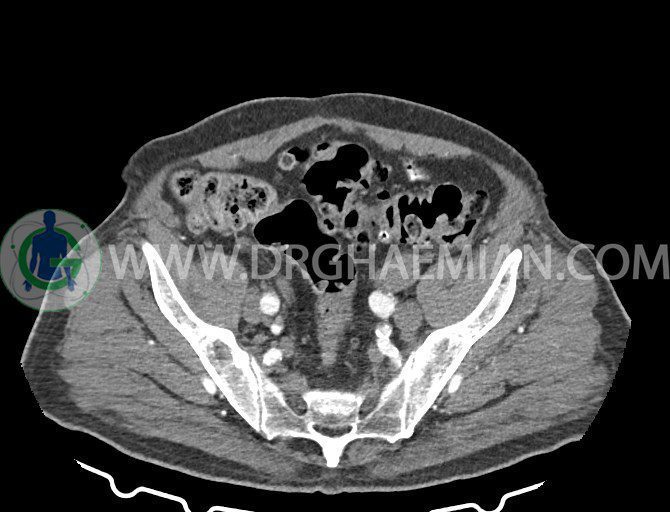

سی تی اسکن لگن یکی از روش های تصویربرداری با سی تی اسکن است. این روش با استفاده از تشعشعات تصاویر عرضی از ناحیه شکمی ایجاد میکند. در این کیس ديورتيكولوزيس، کیست های کورتیکال در هر دو کلیه، لنفادنوپاتی، کلسیفیکاسیون دیواره آئورت و شریان ایلیاک، تغییرات DJD ناحیه توراکولومبار و پروستات بزرگتر از عادی دیده می شود.

در سي تي اسکن اسپيرال شکم و لگن با و بدون کنتراست خوراکی و وريدی (مولتي ديدکتور 16 با مقاطع ظريف و بازسازي هاي ساژيتال و کرونال):

– کلسيفيکاسيون ديواره آئورت و شريان ها ايلياک همراه با نشانه هاي ترومبوز مورال در بيفورکاسيون ائورت با امتداد به پروگزيمال هاي شريان هاي ايلياک

لنفادنوپاتي به ابعاد mm 22 x 25 مجاور شريان ايلياک خارجي چپ و به ابعاد mm 17 x 28 مجاور شريان ايلياک خارجي راست

– پروستات به ابعاد mm 45 x 54، بزرگ تر از نرمال

مشهود است.